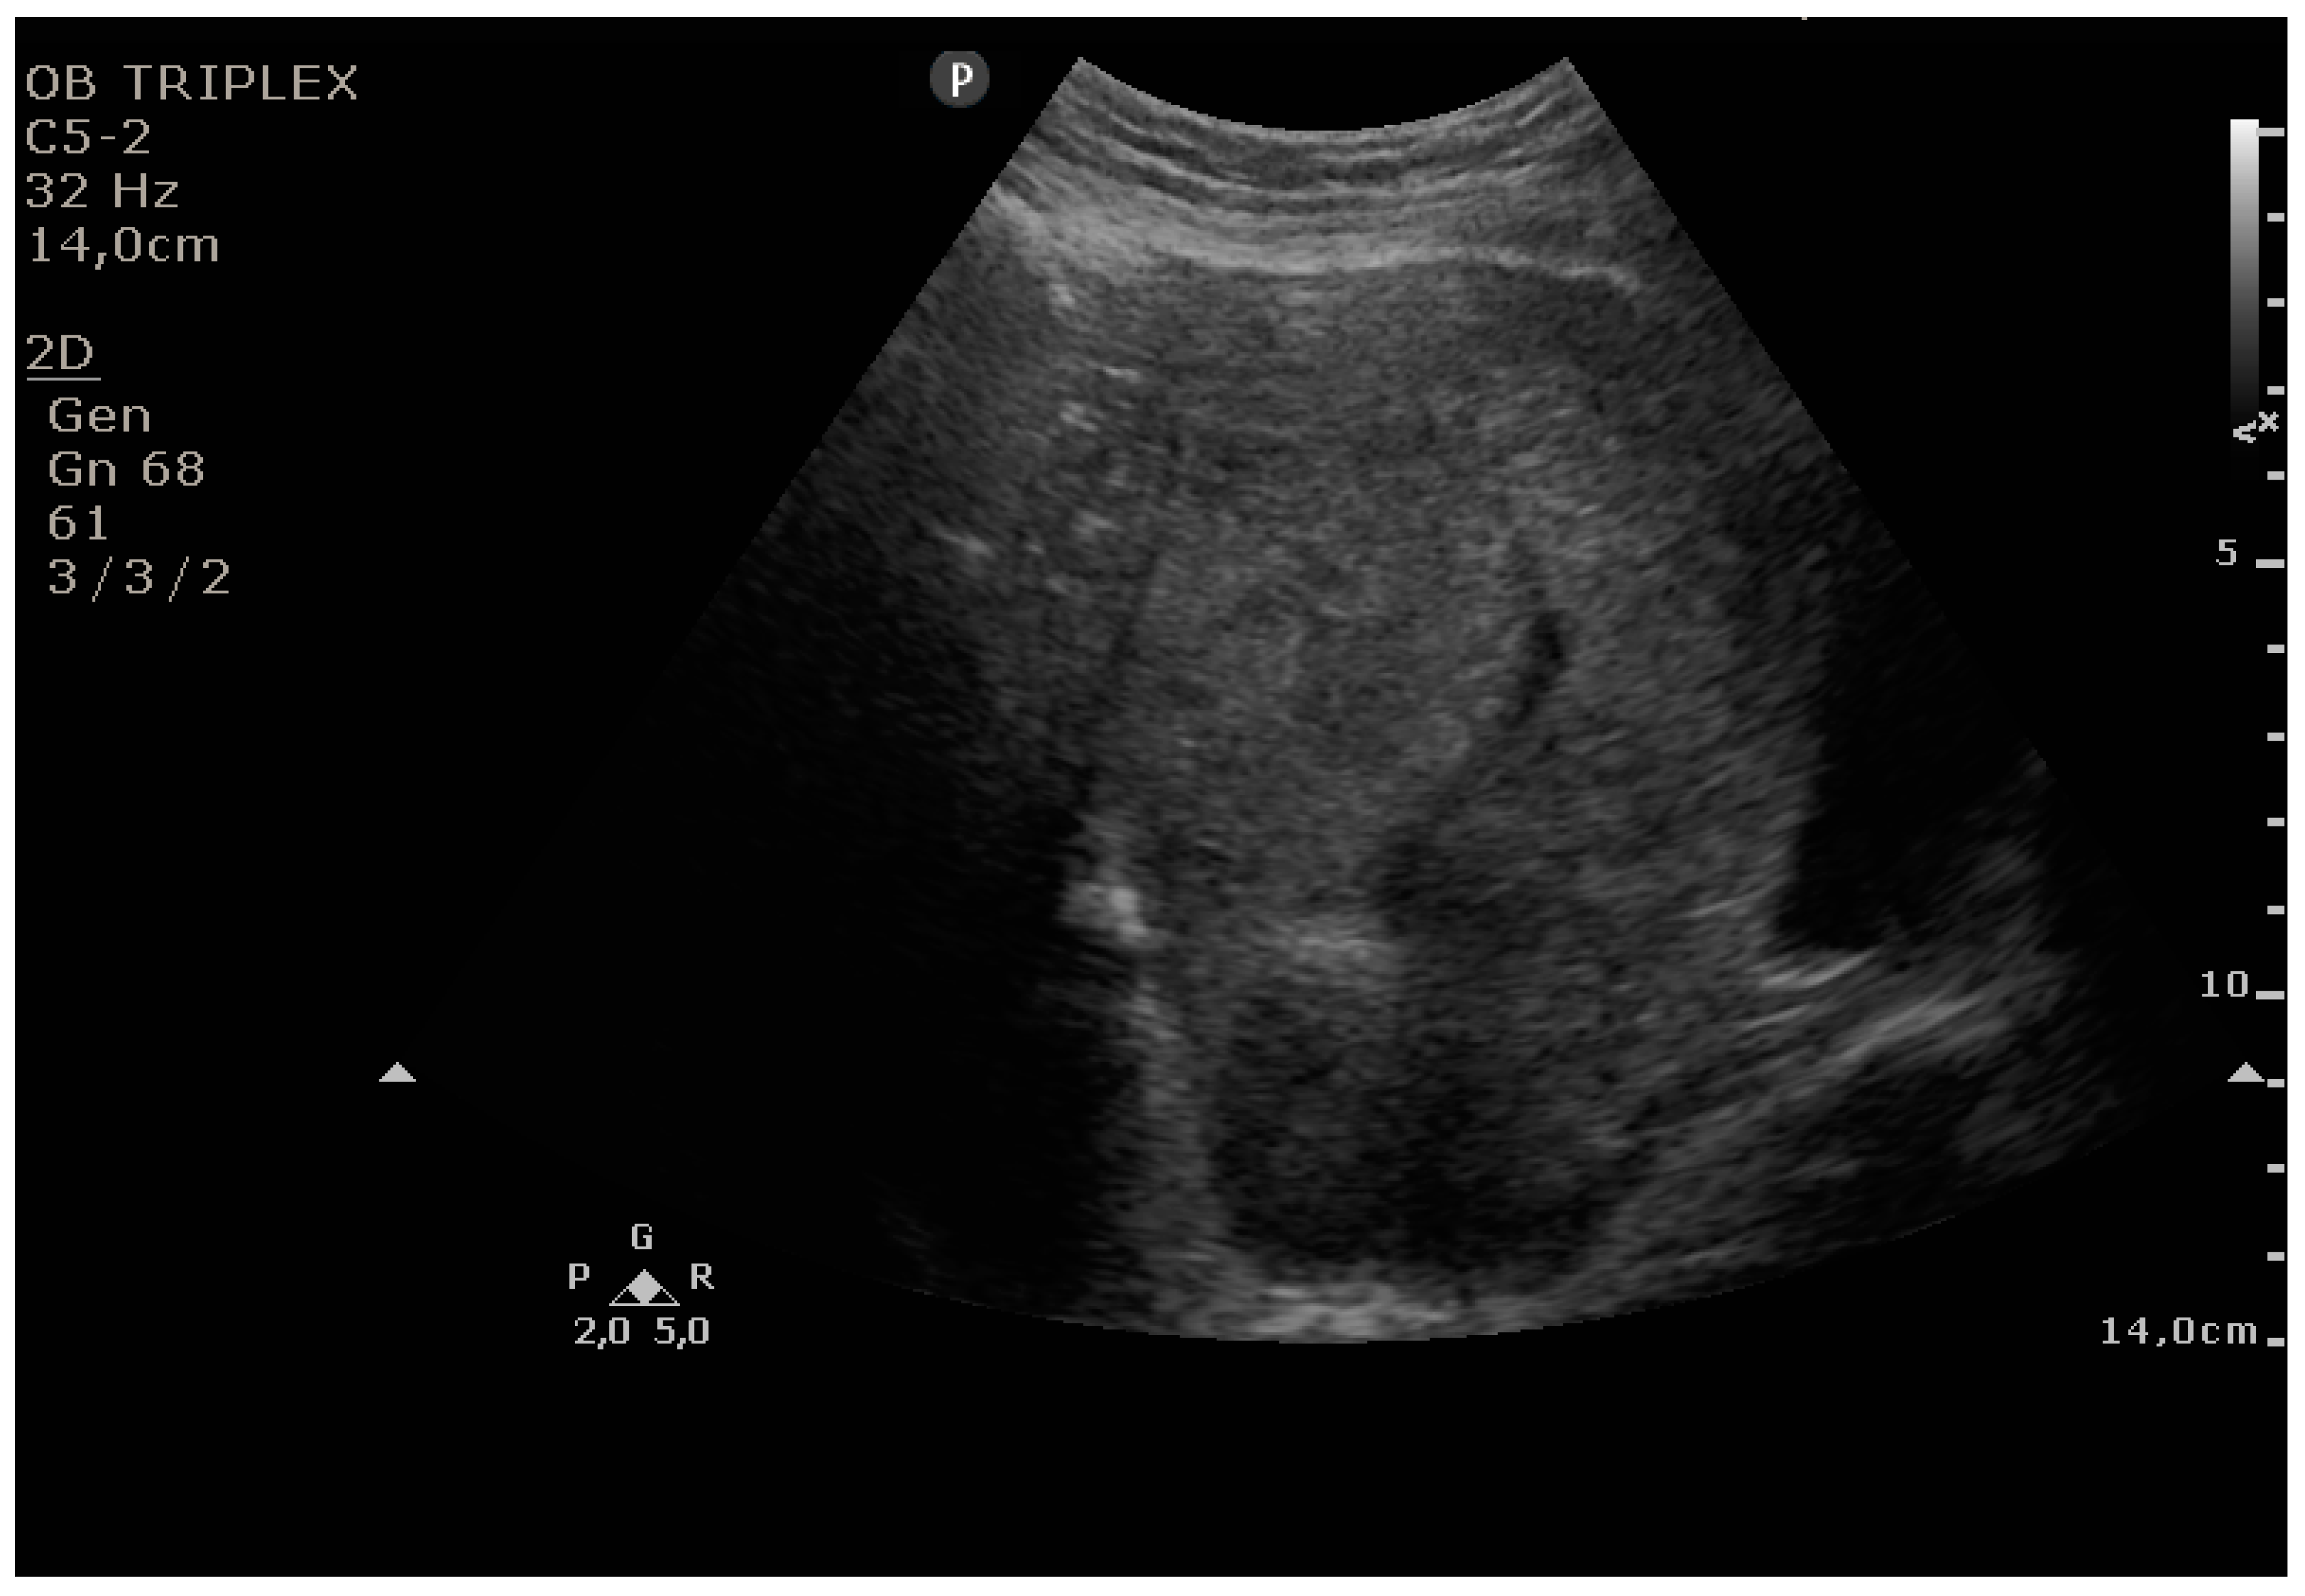

The PUUS method evaluates the proportion of the endometrial length occupied by blood or debris, as follows (Figure 1, Figure 2, Figure 3, Figure 4 and Figure 5):

Grade 2: less than one-half of the endometrial length occupied by blood or debris;

Figure 3. Grade 2: less than one-half of the endometrial length occupied by blood or debris.